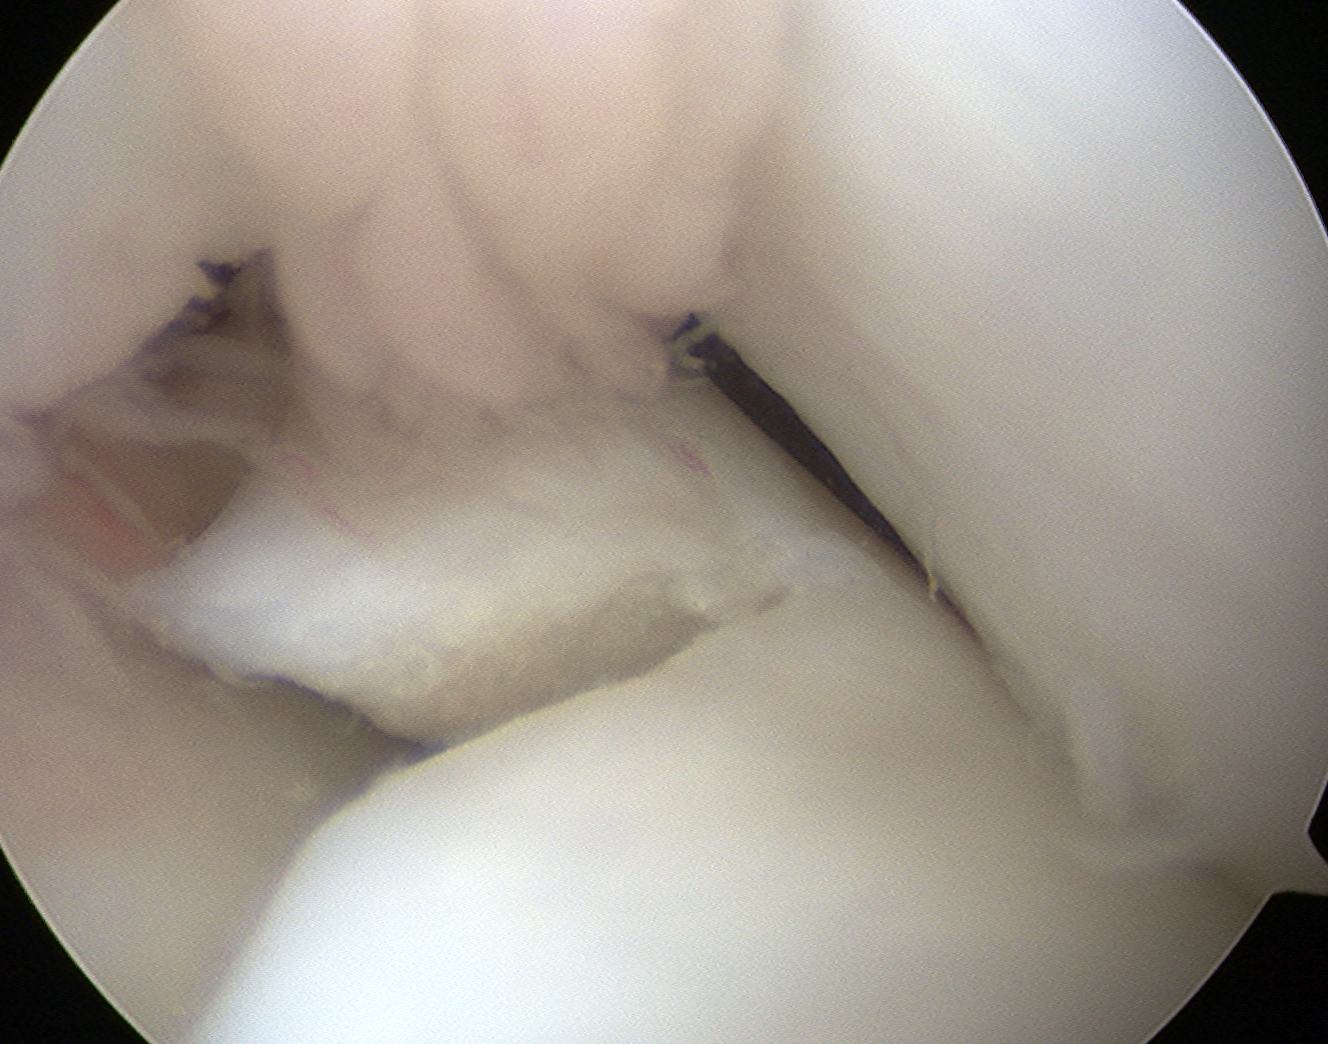

Technique Saucerisation

Technique

- make incision with scissors in medial aspect

- resect posterior part

- saucerise laterally and anteriorly

- need to ensure don't detach anterior horn